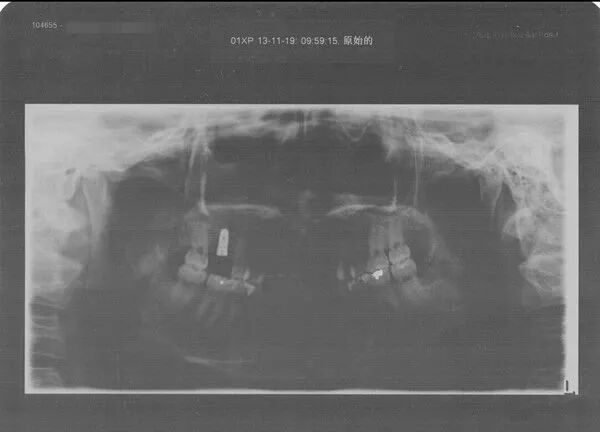

二期手术前,医生还是需要拍X光了解种植体情况。真是不知道拍了多少X光。。。

二期手术主要是牙套相关的一些后续事情。经过咬牙印,选牙齿颜色,我终于戴上牙了 。

我选的BEGO德国种植体,是一家不来梅的公司,当时只有两种选择我也就出于成本选择了相对便宜的那个。